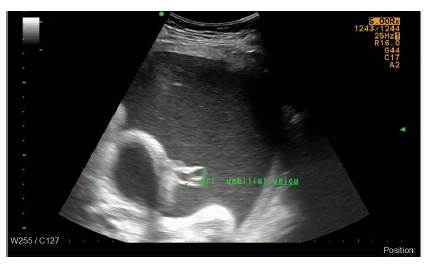

En la ecografía obstétrica de detalle anatómico realizada a las veintiún semanas de gestación, hay persistencia de los hallazgos ecográficos de doble burbuja intraabdominal, presencia de arteria umbilical única y un perfil de crecimiento normal (Figura 2).

Una anotación especial se debe hacer con respecto a la presencia de arteria umbilical única, la cual es un hallazgo frecuente en esta asociación y que desde los últimos años hace parte de la definición dentro de la letra V del acrónimo para anomalías vertebrales o vasculares 7.